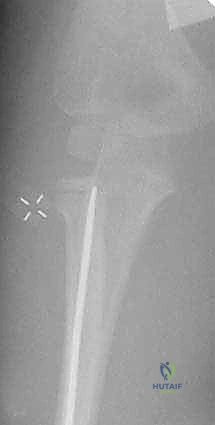

صورة شعاعية تظهر التثبيت النهائي للكسر باستخدام الأسلاك المعدنية المتقاطعة لضمان الاستقرار التام.

لفهم مدى الدقة التي تتم بها هذه الجراحات في صنعاء، نستعرض خطوات تقنية الرد عبر الجلد (Percutaneous Pinning) خطوة بخطوة:

- التحضير والتخدير: يتم تخدير الطفل كلياً لضمان عدم الحركة والألم. يتم تعقيم كامل للذراع وتغطيتها بالمفارش الجراحية المعقمة.

- التموضع (Positioning): يوضع ذراع الطفل على طاولة شفافة للأشعة، مما يسمح باستخدام جهاز التنظير الإشعاعي (Fluoroscopy) بحرية تامة من جميع الزوايا.

- تحديد نقطة الدخول الآمنة: لتجنب إصابة العصب (PIN)، يقوم د. هطيف بوضع الساعد في حالة كب كامل (Full Pronation).

- إدخال الأسلاك (Pin Insertion): يتم إدخال سلك كيرشنر (K-wire) بقطر مناسب (غالباً 1.5 مم إلى 2.0 مم) عبر الجلد، من الجانب الخارجي للمرفق، مروراً برأس الكعبرة، وعبر صفيحة النمو، وصولاً إلى عنق الكعبرة لتثبيت الكسر.